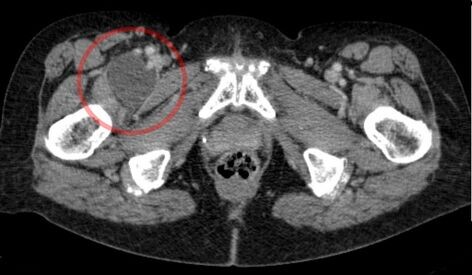

Изображение  демонстрирует значительное увеличение подвздошно-поясничной сумки справа (слева на изображении, выделена кругом) на компьютерной томограмме.

Подвздошно-поясничная сумка — это самая крупная синовиальная сумка в теле человека, присутствующая у 98 % взрослых и расположенная симметрично с обеих сторон.

• Она ограничена спереди мышечно-сухожильными волокнами подвздошно-поясничной мышцы, а сзади — фиброзной оболочкой тазобедренного сустава.

• Сумка тянется от паховой связки вверх до малого вертела бедренной кости вниз, а её боковые границы образованы бедренными сосудами и бедренным нервом.

• В норме она остаётся пустой. Однако при определённых условиях эта сумка может увеличиться в размерах и заполниться жидкостью, что приводит к появлению болевых ощущений и ограничению подвижности.